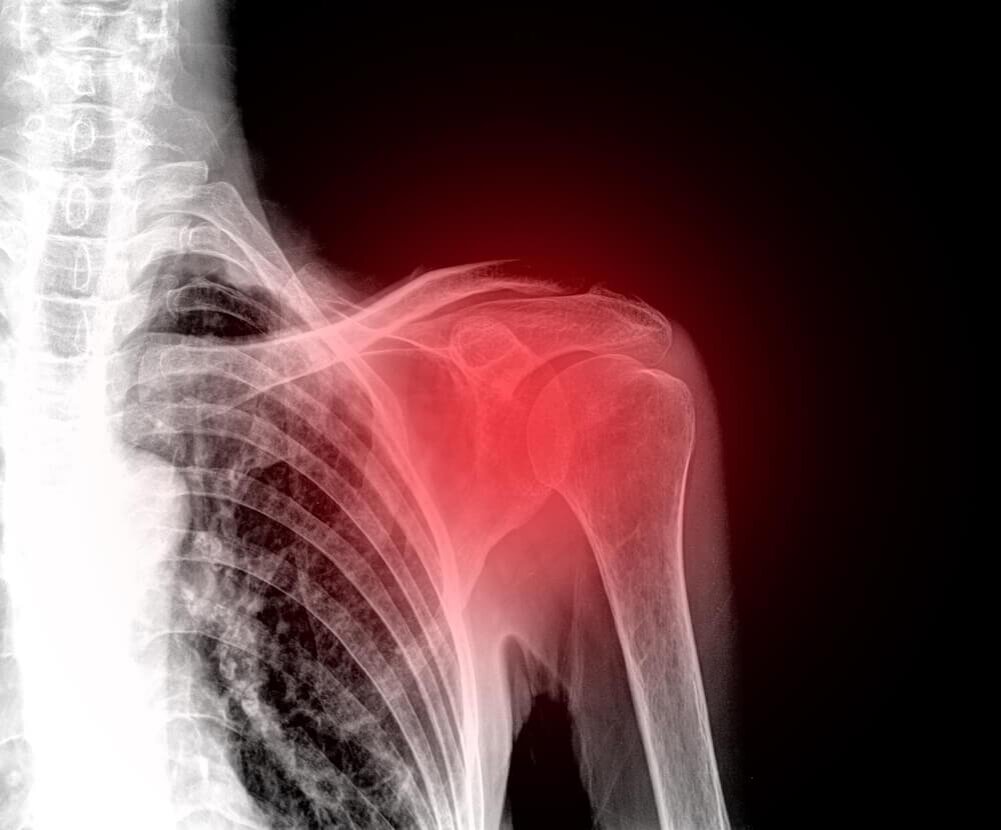

Как снять боль в плече с помощью домашних средств

Хотя боль в плечах - это очень тяжелое состояние, которое делает невозможным выполнение обычных ежедневных дел, вы можете снять его естественным образом, не прибегая к медикаментам. Боль в плече является очень неудобной, так как плечевой сустав позволяет эффективно взаимодействовать с окружающим миром. Есть различные виды травм, которые могут вызвать боль, отек и недвижимость. Также у вас может возникнуть хронический отек, если вы не получите медицинское лечение. Прежде всего следует знать, что боль в области плеча возникает чаще, чем вы думаете. Вам нужно обратиться к врачу в случаях вывихов и переломов. Эти две ситуации, как правило, является результатом травмы в этой области. Патология и частые причины боли в плечах Наиболее распространенными заболеваниями, связанными с болью в плечах, являются: Есть также многочисленные проблемы, которые вызывают дискомфорт: Вывих Это случается, когда головка кости рук вытесняется из гнезда через чрезмерное напряжение, деформацию или удар. Когда

Боль в плече является очень неудобной, так как плечевой сустав позволяет эффективно взаимодействовать с окружающим миром. Есть различные виды травм, которые могут вызвать боль, отек и недвижимость. Также у вас может возникнуть хронический отек, если вы не получите медицинское лечение.

Прежде всего следует знать, что боль в области плеча возникает чаще, чем вы думаете. Вам нужно обратиться к врачу в случаях вывихов и переломов. Эти две ситуации, как правило, является результатом травмы в этой области.